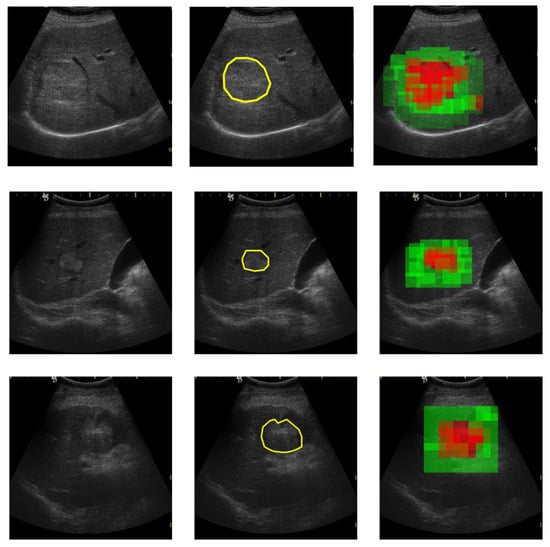

For training the proposed CNN model, the train dataset was augmented by means of rotation, zoom and reflection operations. Rotations in the range [−45 ,45 ], every 5 degrees, and zoom out/in with a factor of 0.8 and 1.2 were applied. A validation set was used for evaluating the classification performance during training. Table 2 shows the distribution of samples per class for training, for validation and for testing. Example images for each class in the two datasets are shown in Figure 3, Figure 4, Figure 5 and Figure 6.

Figure 3. HCC patches from dataset GE7.

Figure 4. PAR patches from dataset GE7.

Figure 5. HCC patches from dataset GE9.

Figure 6. PAR patches from dataset GE9.